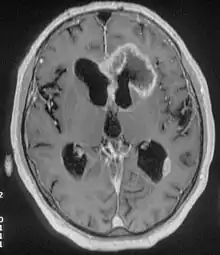

An MRI image of a brain with an invasive, multilocular tumor in the left frontal lobe of the brain.

The origins of frontal lobe seizures can be different deviations.[8] One of the major reasons for FLE is abnormal cognitive development or sometimes congenital abnormal brain development.[8] Other causes are tumors, head trauma, and genetics.[9]